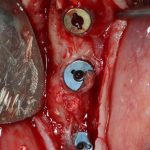

Я зафиксировал костный блок практически без адаптации на несколько винтов. Обрати внимание, что винты находятся в зоне, где не планируется установка имплантатов. Фиксация должна быть надежной, поскольку мне еще предстояла подготовка лунок для имплантатов. Трех винтов для этого вполне достаточно.

Дальнейшая адаптация костного блока свелась к сглаживанию острых краев. После чего я приступил к подготовке лунок и установке имплантатов.

Установка имплантатов.

Напомню, что для этой работы я выбрал субкрестальные имплантаты Ankylos C/X. Они прекрасно сочетаются с любым методом остеопластики.

Глянем на то, что получилось: